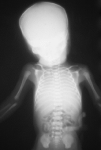

Se practica una radiografía postmortem que informa de la presencia de aire intestinal y pulmonar en las grandes vías aéreas, y de la ausencia de hemivértebras.

El informe autópsico es el siguiente: Feto hembra de treinta semanas de gestación, según peso y longitudes occipito-sacra y del pie, que presenta inmadurez visceral grado II, polimalformado, presentando anomalías faciales, hipoplasia pulmonar (índice peso corporal/peso pulmonar = 0,007), surco simiesco bilateral, bazo supernumerario (0,3 cm) y quiste simple subcapsular hepático (0,2 cm). Las anomalías faciales son las siguientes: Asimetría del tercio facial inferior, con hipoplasia mandibular y de zigoma derechos, microotia derecha con implantación baja de conducto auditivo externo, discreto hipertelorismo, atresia de coanas bilateral, anquiloglosia y paladar ojival con fisura palatina mucosa (ver imágenes adjuntas).

| Figura 1. |

| Figura 2. |

| Figuras 3A, 3B, 3C. |

| Figura 4. |

| Figura 5. |